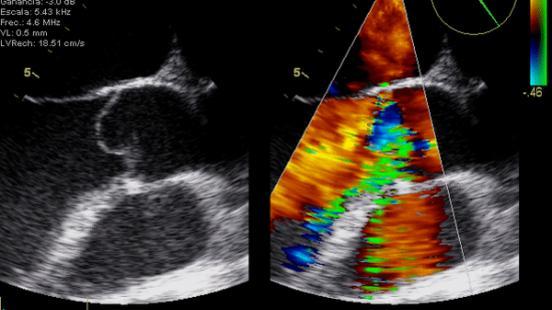

Gracias al uso de ultrasonidos, la ecocardiografia permite estudiar el tamaño, el funcionamiento y los movimientos del corazón. Esta es la técnica diagnóstica más utilizada en cardiología. A pesar de que los cardiólogos son los profesionales sanitarios que mejor dominan este procedimiento, hay otros profesionales que también necesitan conocer cómo funciona. Como explica el Dr. Artur Evangelista, director del Curso Teórico-práctico de Ecocardiografía Básica y de Ecocardiografia Avanzada en Medicina Intensiva, Anestesia y Reanimación, “médicos de familia, internistas o neurólogos también necesitan realizar ecocardiografías para tratar a sus pacientes”. De este modo, el Curso Teórico-práctico de Ecocardiografía Básica y de Ecocardiografía Avanzada en Medicina Intensiva, Anestesia y Reanimación consta de dos partes. “Una primera parte de conocimientos básicos para que estos profesionales, y también los cardiólogos que están empezando, puedan realizar ecocardiografías y detectar posibles problemas. La ecocardiografía te da imágenes de cómo está el corazón, pero estas imágenes, está claro, se tienen que saber interpretar, que es lo que enseñamos en este curso —señala el Dr. Artur Evangelista—. Si estos profesionales detectan alguna posible patología, después pueden derivar al paciente al cardiólogo, que es el especialista”.

El curso ha combinado seminarios teóricos y talleres prácticos para mostrar, entre otros aspectos, las bases de la ecocardiografía y la anatomía ecocardiográfica, la optimización del ecocardiógrafo, el Doppler cardíaco, el uso de la ecocardiografía en el shock, el dolor torácico agudo, el síndrome coronario agudo, la insuficiencia cardíaca, el preoperatorio, la ecocardiografía transesofàgica o la ecografía pulmonar. Uno de los aspectos más destacados ha sido el uso de simuladores, para acercar la formación a las situaciones reales de práctica clínica que se pueden encontrar los profesionales. Los simuladores aumentan la destreza en el estudio y la interpretación de las imágenes y permiten analizar un amplio número de patologías. Esta herramienta se ha convertido en un elemento imprescindible en la formación teórico-práctica en ecocardiografía.